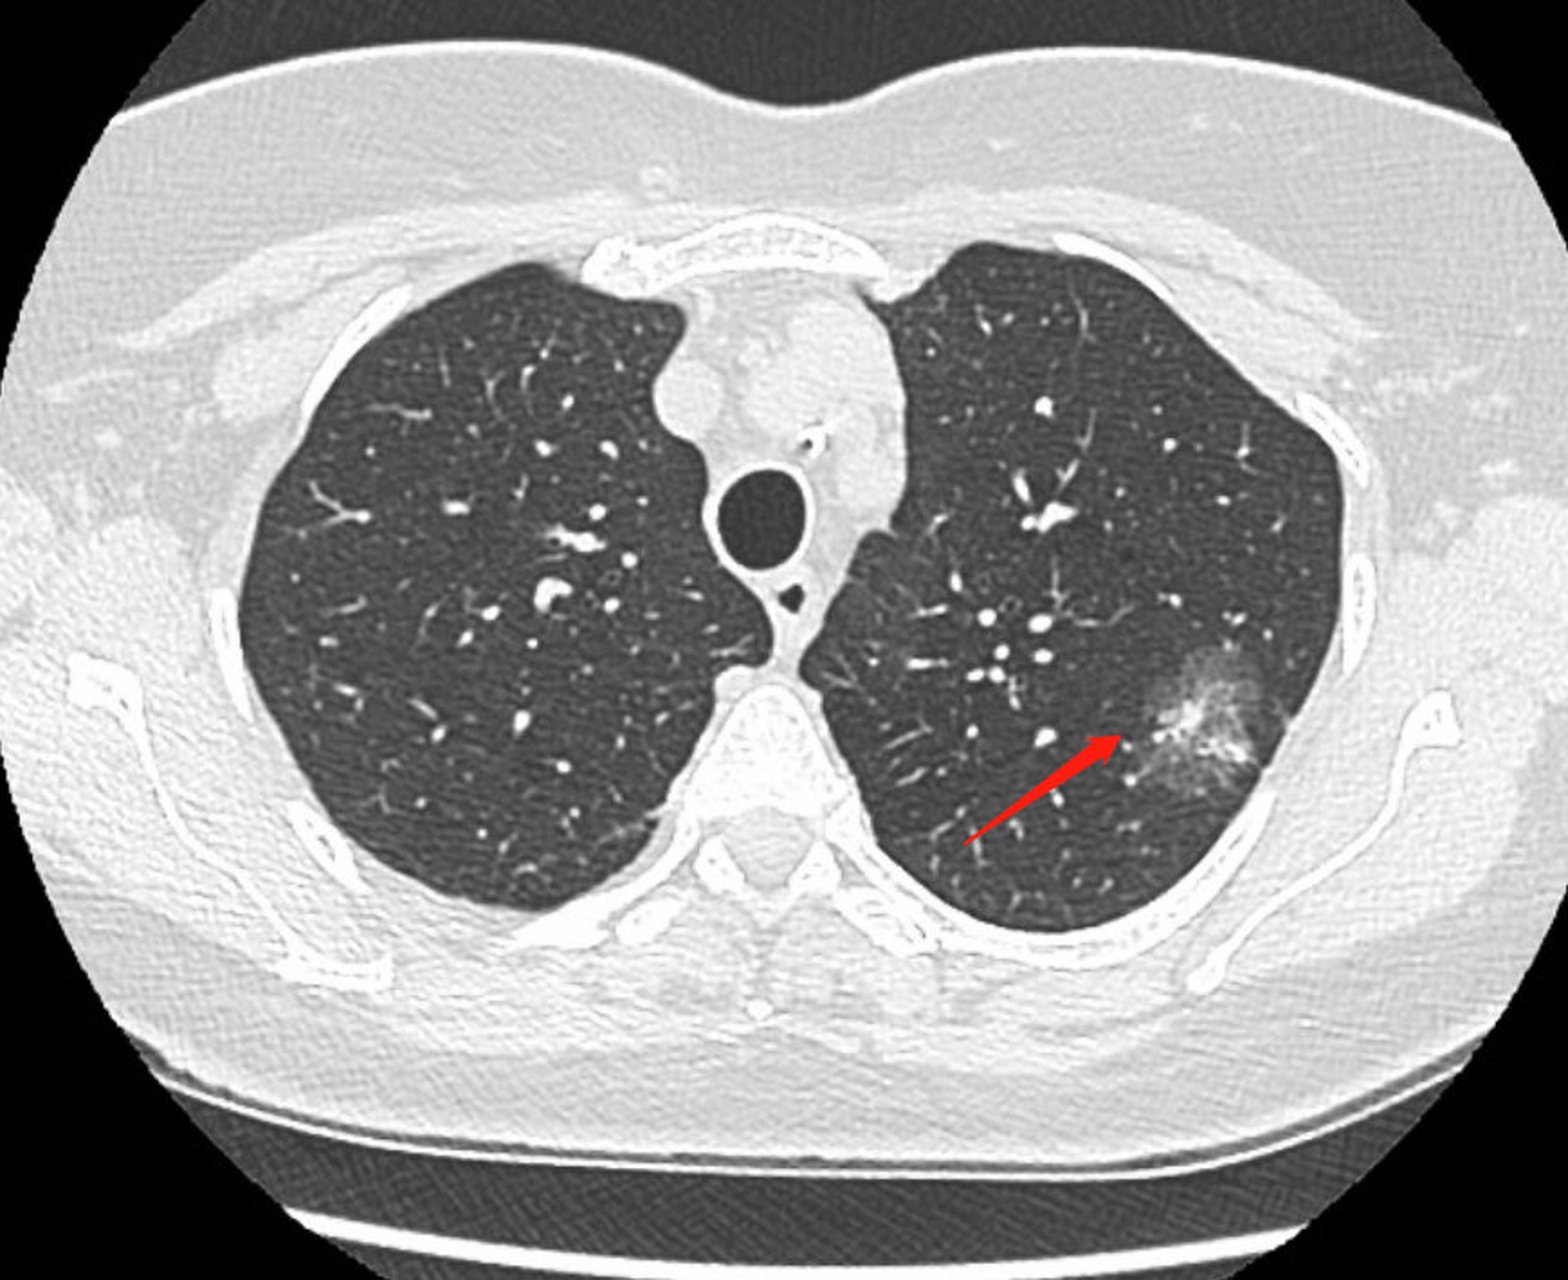

病例金葡菌性肺炎1例ct影像表现